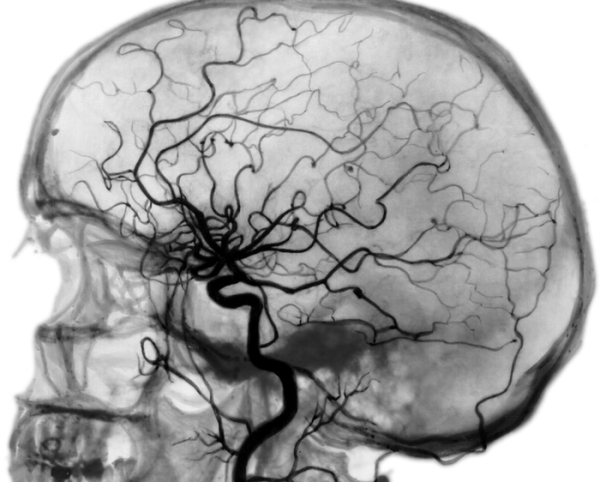

Доступ к сосуду, который подвергается эмболизации, выполняется при помощи направителя и катетера. Иногда он затруднителен и требует большего времени на проведение — это зависит от того, какой орган подвергается лечению. Если точное расположение артерии или вены, снабжающих патологическое образование кровью, неизвестно, используется цифровая субтракционная ангиография (DSA). Изображения, полученные этим путем, применяются для получения доступа к требуемому сосуду методом подбора катетера и направителя.

После изучения полученных данных рентгенографии врач внедряет катетер в бедренную артерию. Эмбол входит в крупный раковый сосуд, перекрывая совсем его просвет. Эмболизация применяется при: